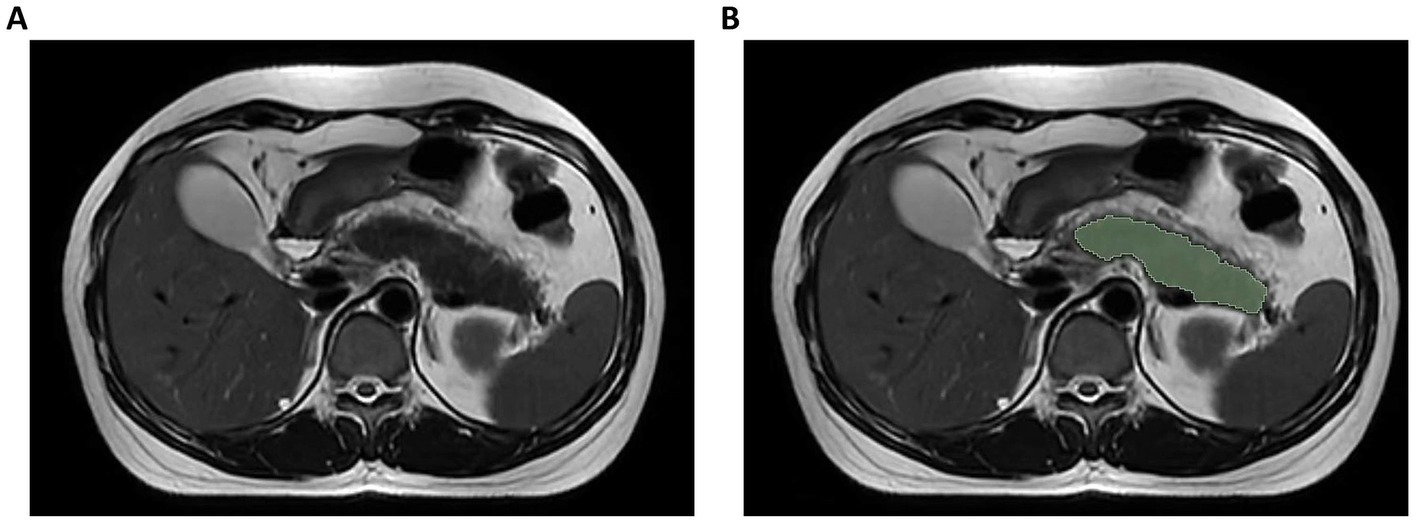

Figure 2

Illustration of axial T2-weighted MRI image segmentation. (A) Original image; (B) Delineation of region of interest.

Pancreatic segmentation was performed manually on T2WI images using 3D Slicer software (v5.2.21) by an experienced radiologist. The pancreatic parenchyma was carefully delineated slice by slice while ensuring the exclusion of surrounding structures such as the intestines, blood vessels, and the common bile duct. When the pancreatic tissue boundaries were unclear in severe cases, T1-weighted and contrast-enhanced images were referenced to improve segmentation accuracy. In cases where necrosis extended into the peri-pancreatic region, only the pancreatic component was included in the region of interest (ROI), while extra-pancreatic necrotic areas were excluded (Figure 2). After applying the Laplacian of Gaussian and wavelet filtering to the original images, 1,223 features were obtained, including shape features, neighborhood gray-tone difference matrix (NGTDM), gray-level size zone matrix (GLSZM), gray-level run-length matrix (GLRLM), gray-level dependence matrix (GLDM), gray-level co-occurrence matrix (GLCM), and first-order features. Of the analyzed patients, one-third were selected randomly, and the target ROI was independently delineated by another senior radiologist blinded to patient clinical data. The interclass correlation coefficient (ICC) was then used to assess inter-observer reliability, with an ICC > 0.75 deemed reliable such that all features clearing this threshold were retained for further analysis.